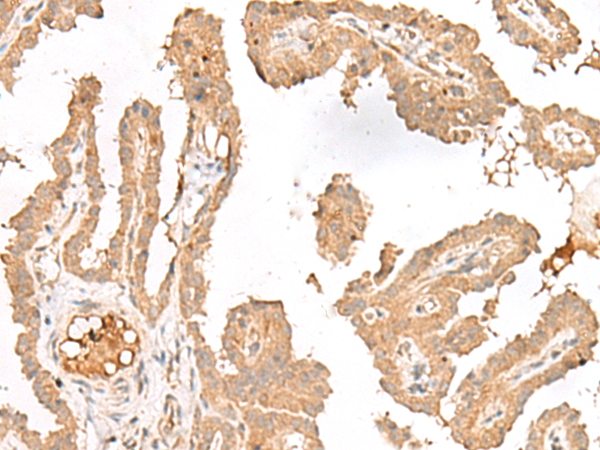

分类: 科研抗体货号: P13458别名: SCN2; GFI-1; GFI1A; ZNF163应用: IHC反应种属: Human, Mouse, Rat